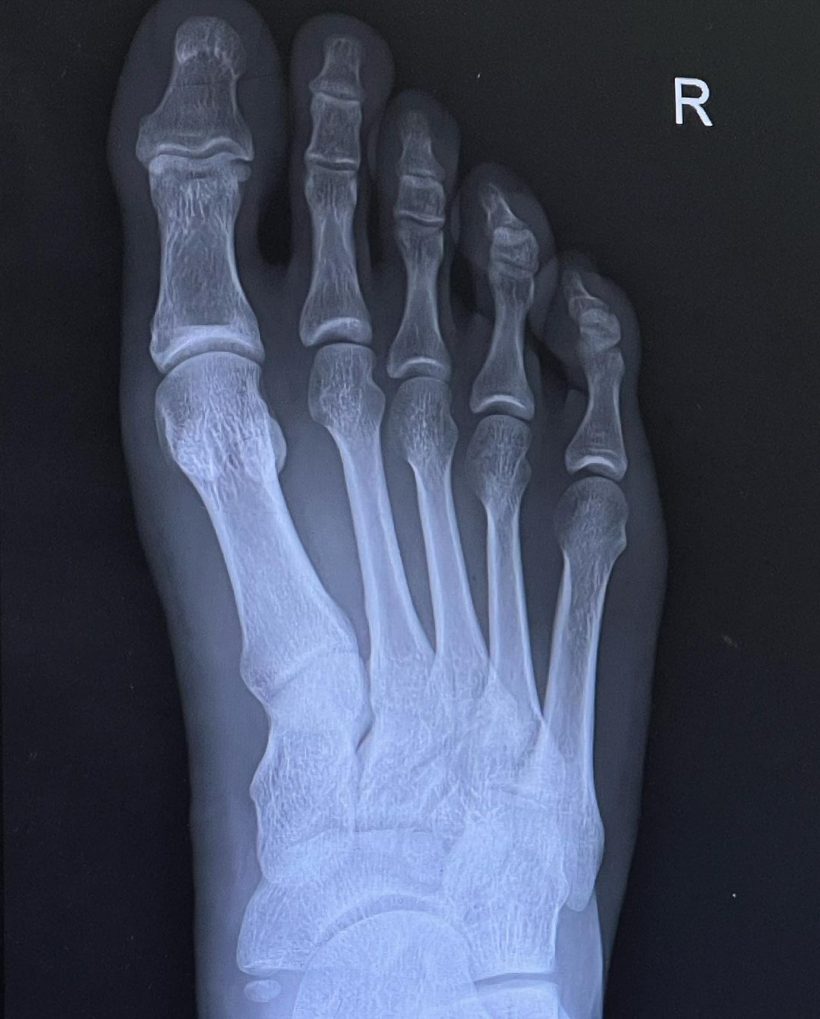

ล่าสุด ค่ำคืนที่ผ่านมา หนุ่มบอส ได้โพสต์ภาพพร้อมเเคปชั่นว่า “เรียบร้อย!! 2-1 🔴 เอ๊ย ผิดครับ!!! เหล็กทับ 👣 เต็มๆ เหล็ก 11 โล (เหล็กล้วนไม่มียางผสม) หลน จากระดับ หัวไหล่ เหลี่ยมลง เท้า เต็ม ๆ จากทรง คือ ดูไงไม่น่ารอด กระดูกน่าจะไม่หัก ก็ ต้อง ร้าว สรุป!! เอ็กซเรย์ ออกมา หมอ บอกเกิ๊นน ไม่เป็นอะไรเลย กระดูกปกติแข็งแรงมาก เอ็นไม่ขาด กล้ามเนื้อไม่ฉีกขาด #ขาผมอดาแมนเที่ยม 🦿เตือนทุกคนนะครับ ใส่รองเท้าทุกครั้งเวลาออกกำลังกายอะไรที่อันตราย หนักจะได้เบาลง ถ้าไม่มีรองเท้าถุงเท้า ผมว่าน่าจะหักละเอียดเลย GYM ไม่ใช่ของเล่นนะครับ 🦾🦿🧠 #เหมือนปีนี้มีแต่เรื่องซวยดีสุดในชีวิตมีแค่เรื่องเดียว“